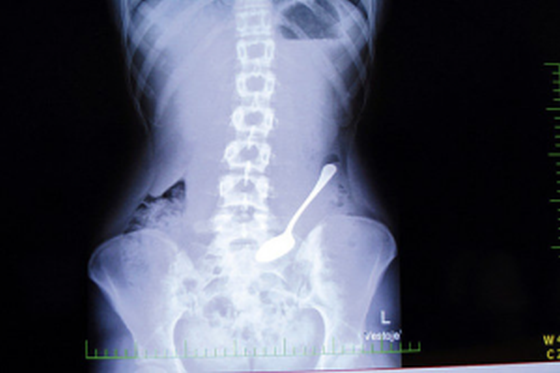

A fugit din spital de frica sa nu-i scoata doctorii coada de lingura pe care o inghitise

În data de 07 iulie 2015, la orele 02.30, poliţiştii locali care patrulau în zona Copou, l-au identificat pe minorul M. L. A., de 13 ani, care figura ca fugit din Spitalul Sf. Maria. Întrebat cum îşi justifică prezenţa în parc la o oră atât de târzie, minorul a declarat că a fugit din spital, deoarece urma să fie operat pentru că a înghiţit o coadă de linguriţă. Din verificări a reieşit că minorul provine din Centrul de Servicii Sociale Tg. Frumos si a fost internat la Spitalul Sf. Maria cu diagnosticul de “ingestie voluntară de corp străin şi tulburare de compartiment”. Minorul a fost predat medicului de gardă din cadrul Spitalului Sf. Maria. Cu o noapte inainte, pe 6 iulie 2015, la orele 23.00, poliţiştii locali au depistat, tot in zona Copou, doi frati minori, S.C., de 7 ani şi S. A., de 8 ani, cu domiciliul în comuna Ciurea, jud. Iaşi, care figurau în evidenţele Poliţiei Ciurea ca dispăruţi. Minorii au fost identificaţi în Parcul Expoziţiei, neputându-şi justifica prezenţa la ora târzie. Copiii au fost predaţi tatălui, care a fost sancţionat contravenţional, conform Legii nr. 61/1991, pentru nesupravegherea minorilor.